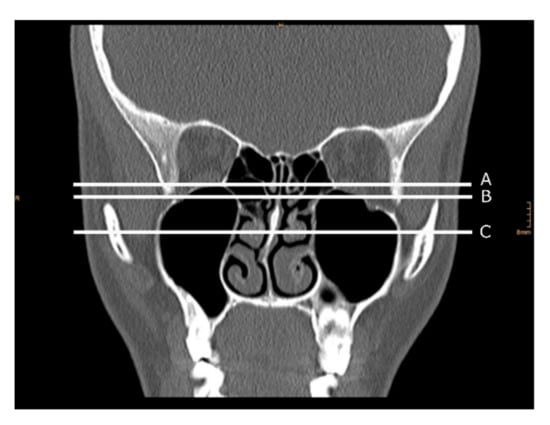

2.3.1. Two-Dimensional Cross-Sectional Analysis